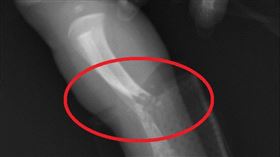

懷孕缺1維生素 女嬰出生1天就骨折

剛出生1天的女嬰,右小腿竟嚴重骨折,被緊急轉送大醫院...